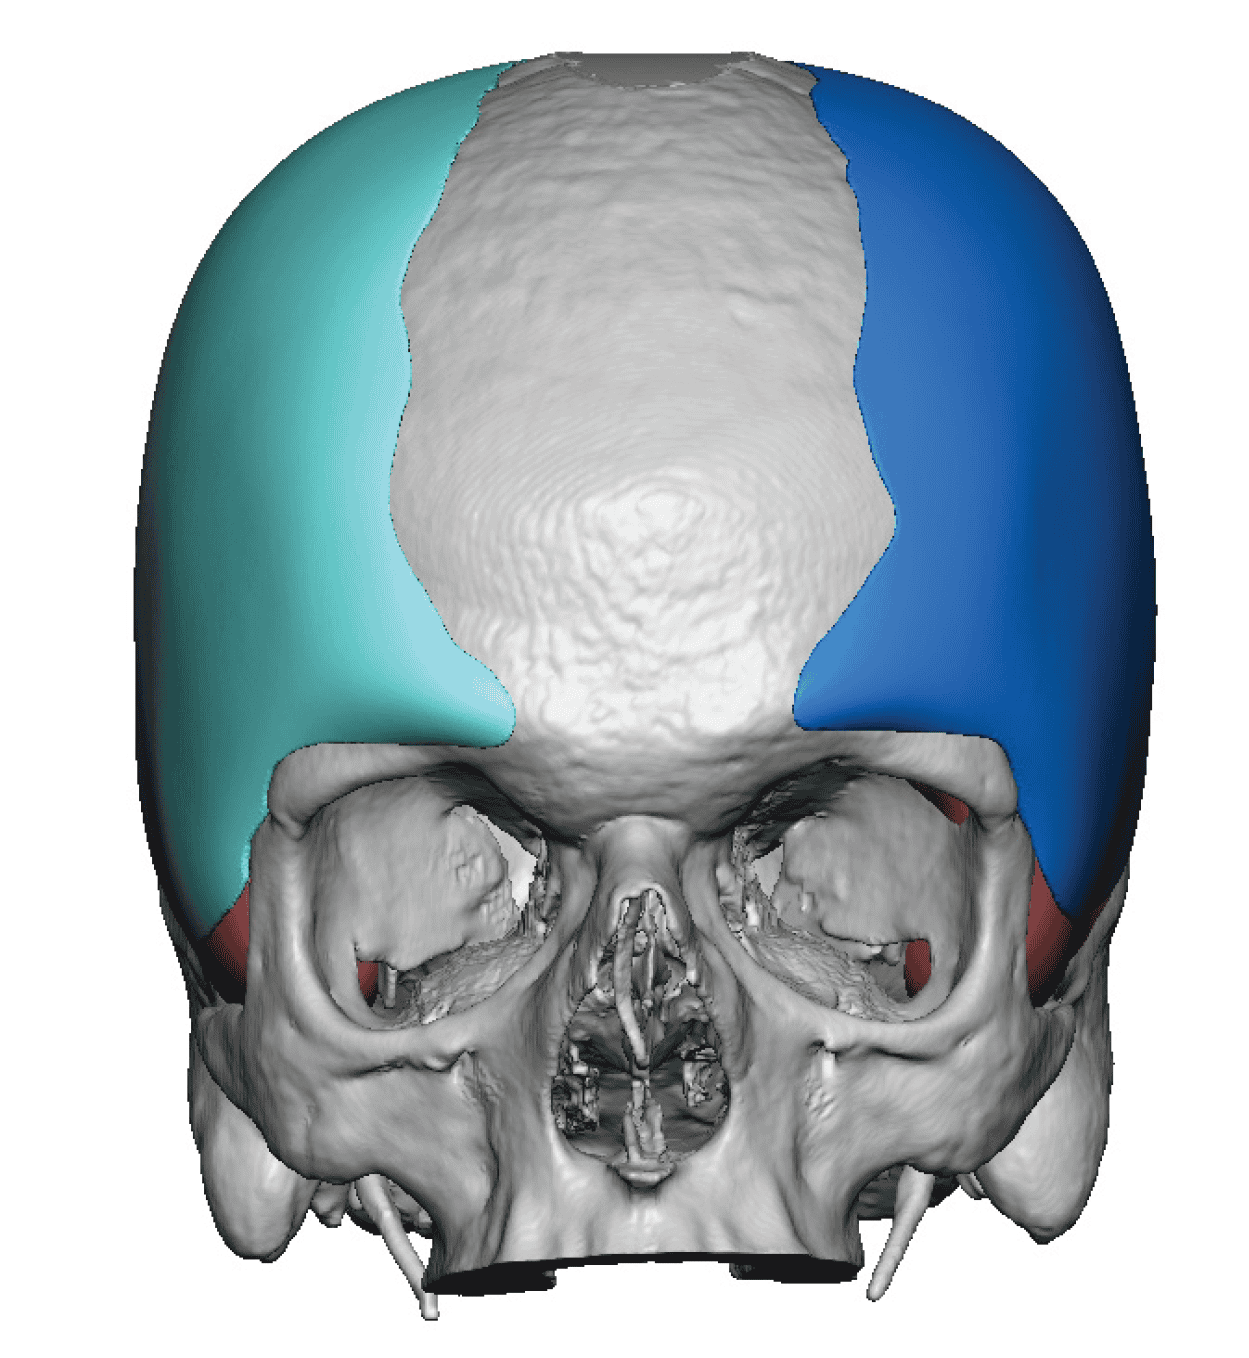

Desire for change of head shape from front view form an inverted V shape to a rounder and wider head shape.

Placement of custom extended forehead-temporal implants through incisions in the crease behind the ear. (he had a prior back of head skull implant which is green in the implant designs and which the head widening implants partially covered it)

Desire for change of head shape from front view form an inverted V shape to a rounder and wider head shape.

Placement of custom extended forehead-temporal implants through incisions in the crease behind the ear. (he had a prior back of head skull implant which is green in the implant designs and which the head widening implants partially covered it)